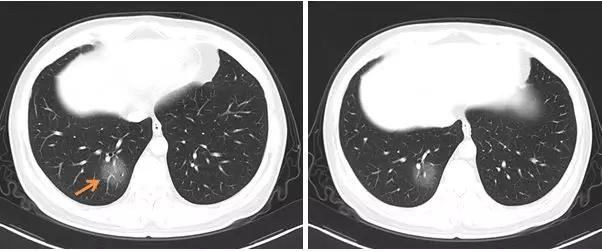

右肺下叶后基底段单发磨玻璃样病变

最为典型和有特征的早期表现:

胸膜下斑片状磨玻璃影,多发、单发都可以;其纹理可呈网格样(铺路石征)

1. 早期病变为局部斑片状亚段分布为主;